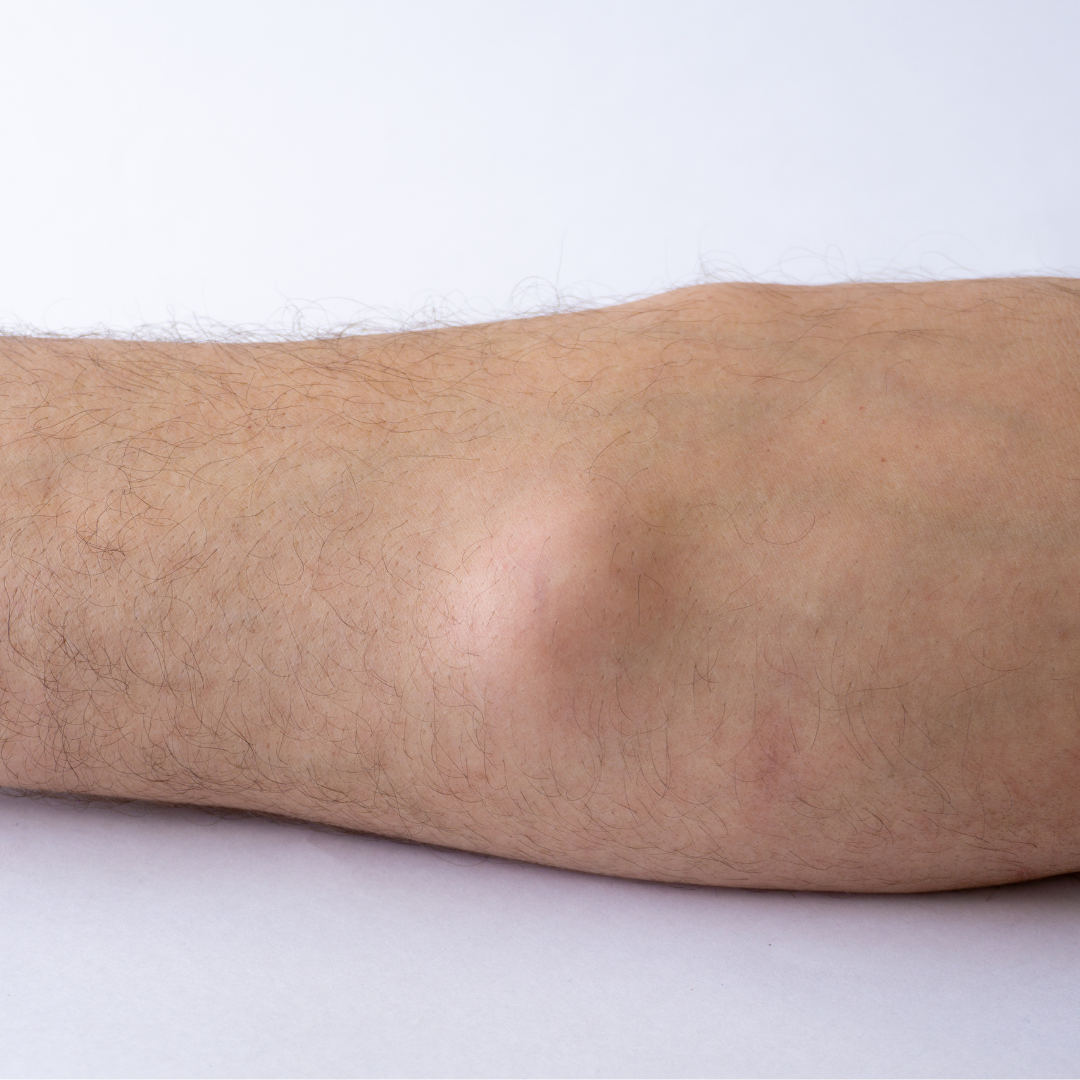

Understanding Lipomas:

Lipomas are benign, soft tissue tumors that commonly develop just beneath the skin. While they are generally harmless, their presence can be a cause of concern for aesthetic and comfort reasons. Dr. Preethi B Nayak & Dr. Vivek M Pai and our expert team at Experia Advanced Skin & Hair Clinic recognize the importance of addressing these concerns and offer specialized Lipoma Surgery solutions.